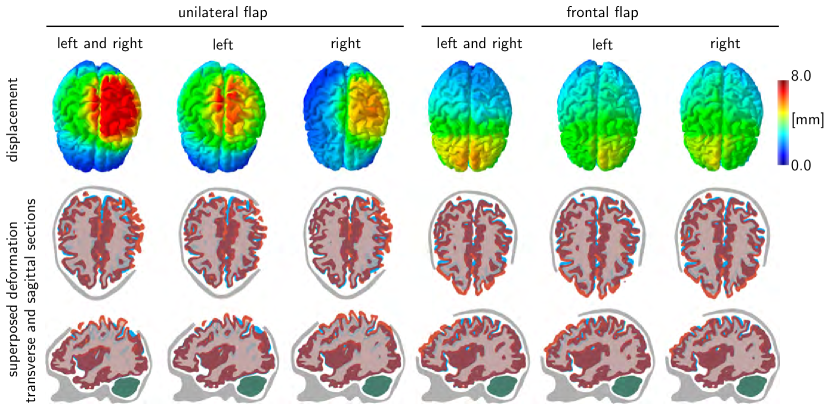

We simulate three different cases of swelling, in both hemispheres, exclusively in the left hemisphere, and exclusively in the right hemisphere. To release the swelling-induced pressure, we simulate two different decompressive craniectomies, a frontal flap with 4,279 skull elements removed and a unilateral flap with 2,494 elements removed. For all cases, we quantify and compare the mechanical response in terms of the overall deformation, the maximum principal strain, the radial and tangental stretch, and the midline shift. The midline shift is a common clinical indicator to characterize the degree of subcortical swelling and axonal damage.

Refer to caption

Figure 7: Decompressive craniectomy. Displacement and superposed deformation in transverse and sagittal sections for unilateral and frontal flaps with left and right, left, and right hemispherical swelling. Swelling causes a shift of intracranial tissues, a key indicator of the trauma’s severity in clinical practice. The midline shift of the cortical and subcortical layers highlights the immediate release of tissue strain upon removal of the unilateral and frontal flaps.

Figure 7 illustrates the displacement and the superposed deformation in transverse and sagittal sections for unilateral and frontal flaps with both left and right, only left, and only right hemispherical swelling. The surgical area available for a frontal flap is about twice as large as the area for a unilateral flap. Consequently, for the same amount of swelling, the displacements of the frontal flap are significantly smaller than for the unilateral flap. This finding is in agreement with our intuition and with our idealized hemidisk simulation in Figure 3, for which larger opening angles generate smaller radial and tangential stretches. The superposed deformation in transverse and sagittal sections in Figure 7 highlights the relative motion of different regions of the brain as the brain bulges outward. Swelling naturally causes a shift of all intracranial tissues. The shift of the midline, which is clearly visible in this sequence of images, is a key clinical indicator for the degree of trauma.